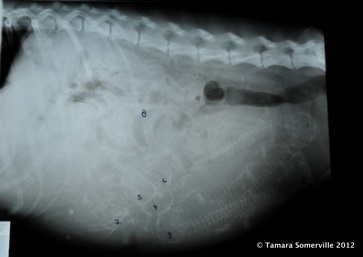

One week before the due date, an X-ray provided another estimate on the litter size (eight puppies were clearly visible) and indicated that the puppies were all about equal size and lined up for a safe delivery.

Jan sorted color-coded yarn to identify the puppies.  She bought nine different colors because the x-ray on Monday, March 26, had indicated at least eight puppies, with a possibility for a ninth.